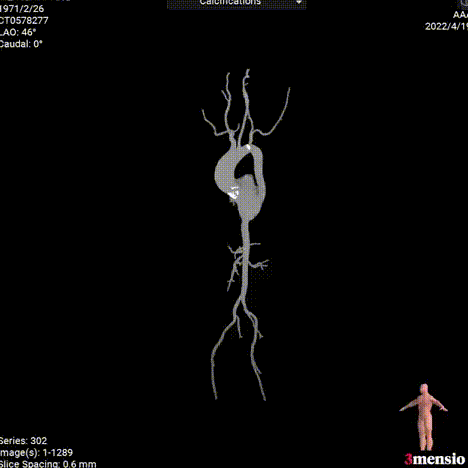

3.升入动脉瘤样扩张,增加导丝跨瓣难度,升入动脉风险高。

4.横位心,瓣膜过弓跨瓣难度高。

瓣膜释放后主动脉根部造影:瓣膜释放后形态位置良好,造影无反流。

术后即刻压差7mmHg,流速1.3m/s,EF41%。